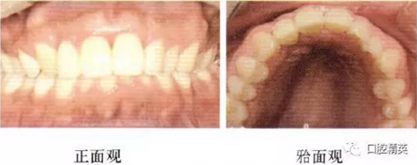

患者選擇211的樁核冠修復(fù)。首先制作診斷蠟型,臨時罩面mock—up,讓患者對最終的修復(fù)體有一個預(yù)估,滿意后進(jìn)行常規(guī)的牙體預(yù)備,取模,戴牙。治療前后對比口內(nèi)像見下圖(圖11,12)。

圖11 治療前口內(nèi)像

圖12 治療后口內(nèi)像